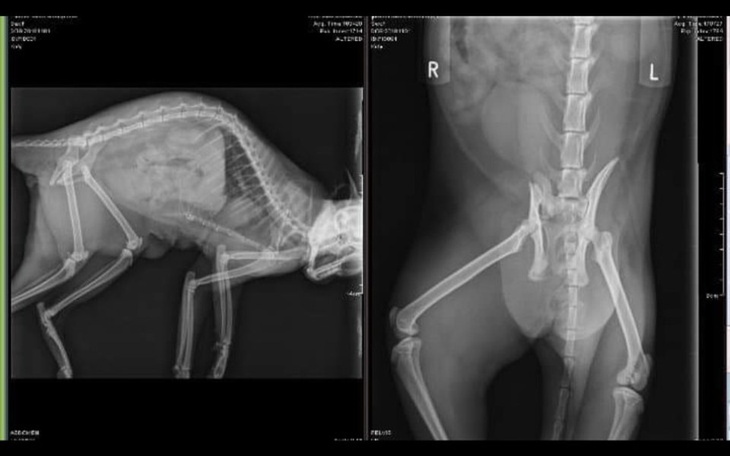

W poniedziałek miała wizytę kontrolną, Dr. Radek powiedział, że wszystko sie pięknie goi, nie ma powikłań, a co najważniejszej wraca jej czucie w łapce, w ktorej wcześniej było bardzo slabe❣

Kicia nie może się jeszze załatwiać, dostała specjalne leki, za 11 dni kolejna wizyta kontrolna!

Pusia została adoptowana z naszego Stowarzyszenia przez wolontariuszkę Paulinę oraz jej mamę . Kilka dni temu zadzwoniły do nas zapłakane prosząc o ratowanie jej życia... Niestety nie stać nas na opłacenie operacji oraz rehabilitacji, która konieczna jest aby uratować życie ich członka rodziny. Z tego powodu postanowiliśmy zorganizować tę zbiórkę, wiemy, że dzięki Wam - naszym przyjaciołom i zwierzolubom jesteśmy w stanie uratować kolejne kocie życie!